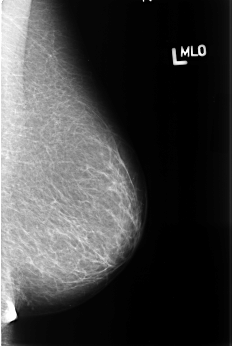

B_3394_1.LEFT_MLO

LEFT_MLO LINES 4488 PIXELS_PER_LINE 3016 BITS_PER_PIXEL 12 RESOLUTION 50 NON_OVERLAY